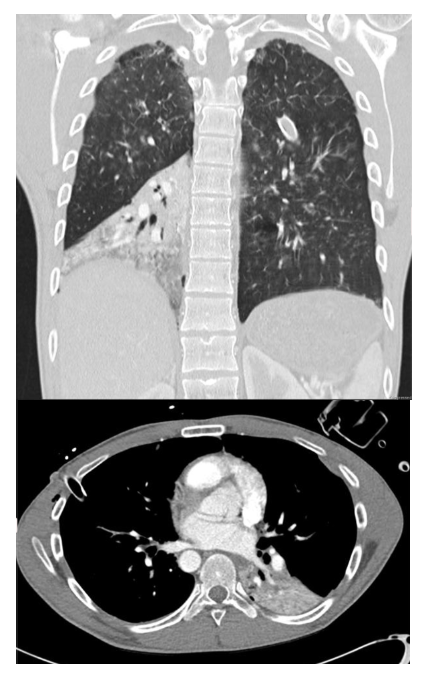

What are the features of RML collapse on CT scan

CT features: (4)

Triangular opacification abutting R heartborder, thinner at the hilum in axial image

Horizonal fissure rotates anteromedially

Oblique feature bows anteriorly

RUL rotates anterolaterally and RLL rotates posterolaterally and meets lateral to the collapsed RML

What are the features of RML collapse on CXR?

CXR features: (7)

R mid to lower air space consolidation – can be subtle in PA, so lateral CXR can help

Horizontal fissure no longer visible

Obscured R heart border